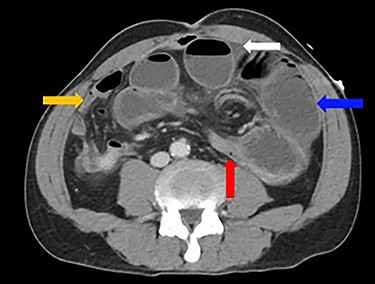

A 52-year-old man presented with a 1-day history of generalized abdominal pain, distension and vomiting. Two years prior, he underwent a subtotal colectomy for colorectal cancer associated with Lynch syndrome and adjuvant chemotherapy. He was haemodynamically stable on presentation. Examination revealed a soft abdomen with marked distension and left periumbilical tenderness, however, no peritonism. Biochemistry showed lactate: 1.9, white cell count: 17 and C-reactive protein: 10. Computed tomography (CT) abdomen demonstrated a closed-loop SBO with transition point mid-abdomen, free fluid but no free gas (Figs 1 and 2). The patient was resuscitated with intravenous fluids, a nasogastric tube was inserted and they proceeded to an exploratory laparotomy for the closed-loop SBO. Intra-operative findings noted a loop of distended small bowel adherent to the anterior abdominal and pelvis side walls, with a loop of ileum twisted at the mesentery secondary to a band adhesion causing the closed-loop obstruction. The patient underwent adhesiolysis and untwisting of the mesentery, which demonstrated viable ileum with no evidence of perforation. In addition, the liver was smooth, there was no evidence of peritoneal metastases and the previous side-to-side ileo-sigmoid anastomosis was intact with no evidence of stricture or cancer recurrence. Lastly, milky intra-abdominal fluid was noted intra-operatively, with a sample sent for biochemistry showing a triglyceride level of 1584 mg/dl indicative of CA. Post-operative recovery was delayed by a prolonged ileus for which they were commenced on total parenteral nutrition (TPN) and slowly upgraded to a low-fat diet following resolution of the ileus. They were discharged home on Day 49 post-operatively.

Dilated loops of small bowel (blue arrow), transition point (red arrow), free fluid (evidence of CA; white arrow) and collapsed small bowel (orange arrow).